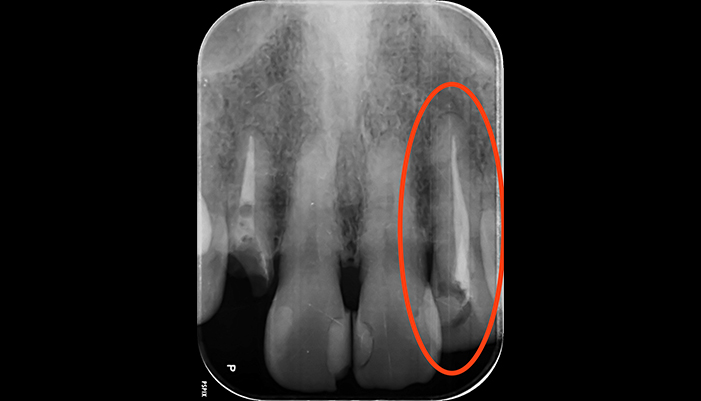

治療前

治療後

| 主訴 | 虫歯を治したい |

|---|---|

| 治療期間 | 1回 |

| 費用 | 再根管治療132,000円(税込)+ ファイバーコア44,000円(税込)= 176,000円(税込) |

| 治療内容 | ラバーダムを用いて無菌的な環境下で再治療(過去に根管治療をしている歯の治療)を行いました。 過去に詰めた修復物の周りが虫歯になってしまっていたため、マイクロスコープ下で虫歯を完全に取り切り、 NiTiファイルを用いた根管形成、薬液や超音波器具による洗浄、体に馴染みの良い材質による充填、被せ物を支え、再感染しないように土台を立てました。 |